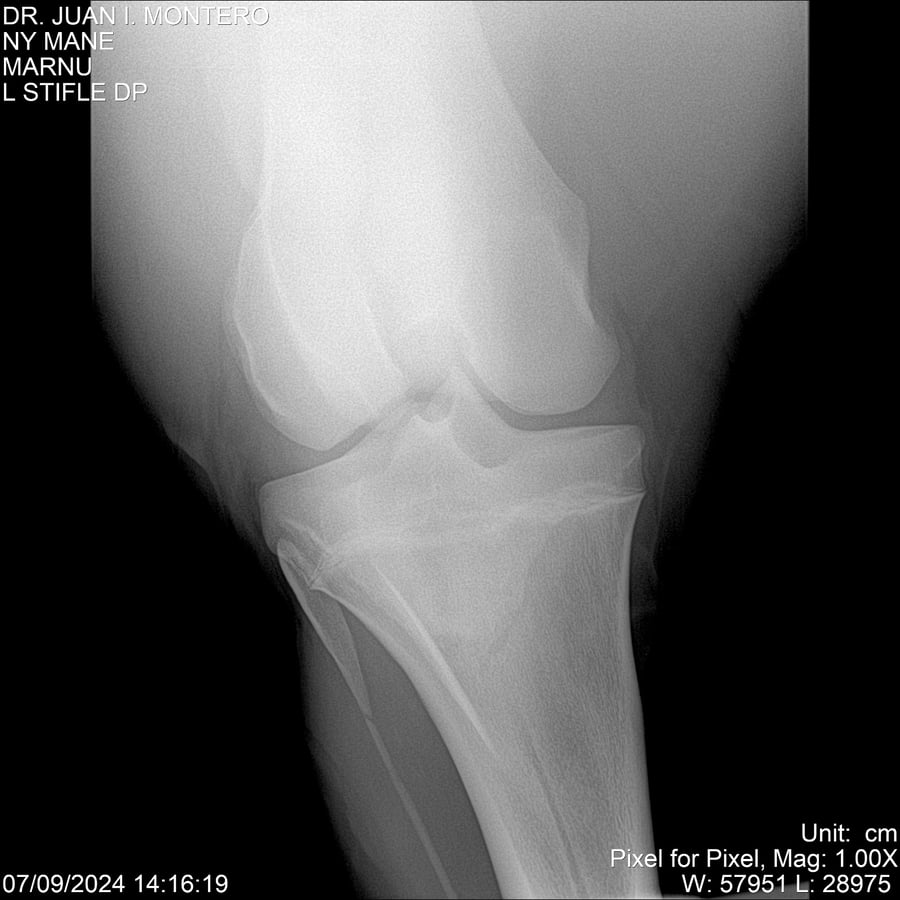

LOTE 20, NY MANE Lote Anterior Volver al remate Lote Siguiente Ficha Contacto Montevideo - Ficha del Lote Identificador: #282520 Categoría: Yeguarizos 76 Visualizaciones ClicData Contacto Empresa: Abelenda N. R., Walter Hugo Nombre*: Teléfono* : E-mail* : Mensaje Enviar Registrese gratis Este contenido Exclusivo está disponible sólo para usuarios registrados Ingresar